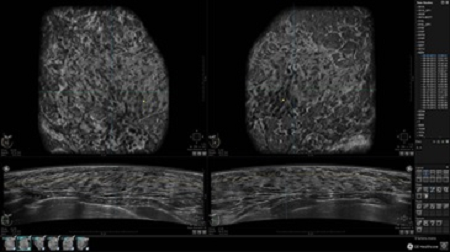

• Получение объемных 3D изображений с возможностью покадрового просмотра

• Отображение объемных 3D ультразвуковых изображений, которые состоят из традиционных поперечных и воссозданных коронарных и сагиттальных проекций

• Многооконный просмотр: 4 - 12 изображений

• Стандартизованная ориентация изображения: «толстый срез» в коронарной плоскости; поперечная; сагиттальная плоскость; радиальный и антирадиальный поворот изображения; просмотр исключительно области интереса

• Одновременный просмотр двух изображений для сопоставления в коронарной плоскости